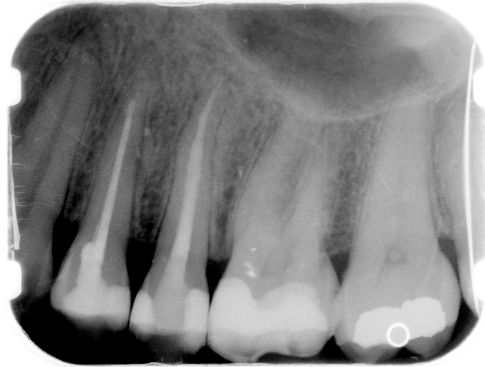

ad a. Een vijl die bijna uitsteekt inde pulpakamer.

Maak de vijl goed zichtbaar door eventueel overhangend dentine te verwijderen. Probeer met een

ultrasone tip

de vijl los te trillen. Lukt dit niet, prepareer dan met ultrasone tips plus minus 3 mm naar apicaal toe langs de vijl enige ruimte te creëren.

Probeer de vijl vast te klemmen in het IRS instrument

.

Trek de vijl voorzichtig uit het kanaal.